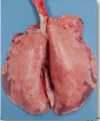

Pleurisy

A form of fibrinous pneumonia.

General rule

Drier beige deposits = more longstanding lesions